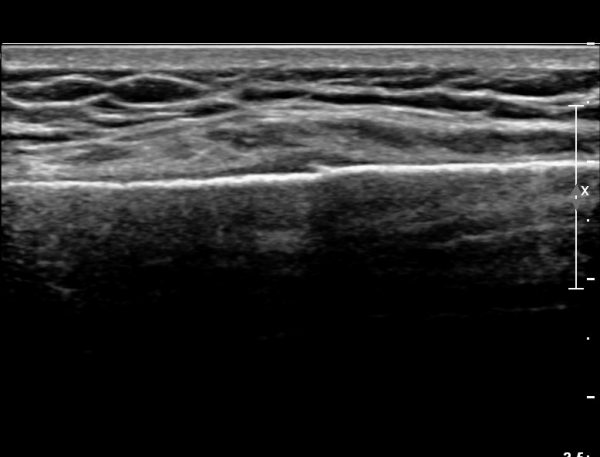

ÃÊÀ½ÆÄ °Ë»ç : ¼Õ¸ñ ¼ö±Ù°ü ±ÙÀ§ºÎ Ⱦ´Ü¸é°Ë»ç¿¡¼­ Äá¾Ë»À Ç¥ÃþÀ¸·Î ¾à°£ÀÇ ¿¬ºÎÁ¶Á÷ ºÎÁ¾ÀÌ °üÂûµÊ(»çÁø 1).